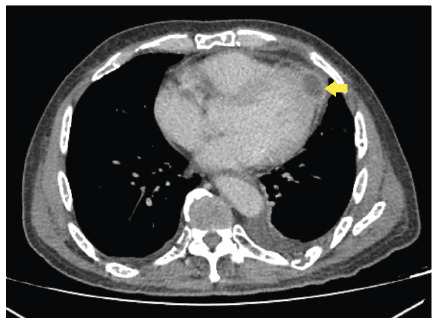

Pericardial abscess: A rare complication of disseminated melioidosis in a patient with relapsed multiple myeloma.

心包脓肿:复发性多发性骨髓瘤患者弥散性类瘤病的罕见并发症。